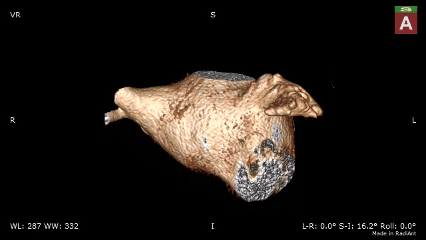

CT三维重建评估

低位菜花型左心耳

该心耳为菜花型左心耳,开口类圆形;

患者左心耳呈多分叶菜花型,开口为类圆形,上下开口不对称,腰部缩窄,远端梳状肌发达,内部空间有限。